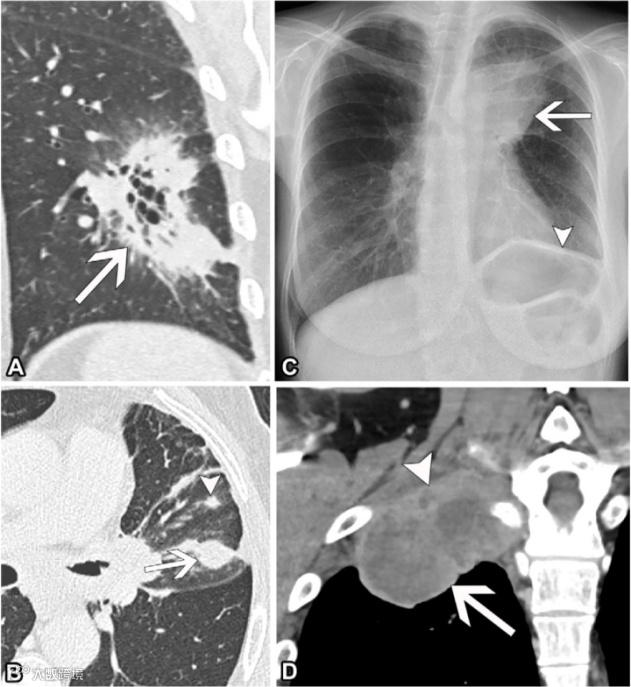

图3. 四例T3期肺癌患者。

(A)71岁女性非小细胞肺癌(NSCLC)患者的冠状重建非增强胸部CT图像(肺窗),显示左下叶有一个肿块(箭头),最大平面尺寸为5.8厘米。

(B)68岁男性NSCLC患者的轴位非增强胸部CT图像(肺窗),显示左上叶的原发肿瘤(箭头),并在同一叶内有一个独立的肿块结节(短箭头)。

(C)62岁女性NSCLC患者的后前位胸部X光片,显示左上叶的肿块(箭头),侵犯左膈神经(未显示),导致左膈肌升高(短箭头),因左膈神经受累所致。

(D)46岁男性NSCLC患者的冠状重建增强胸部CT图像(软组织窗),显示右侧上纵隔肿瘤(箭头),侵犯胸壁和第一肋骨(短箭头),但未侵犯椎骨、脊髓管或臂丛神经。